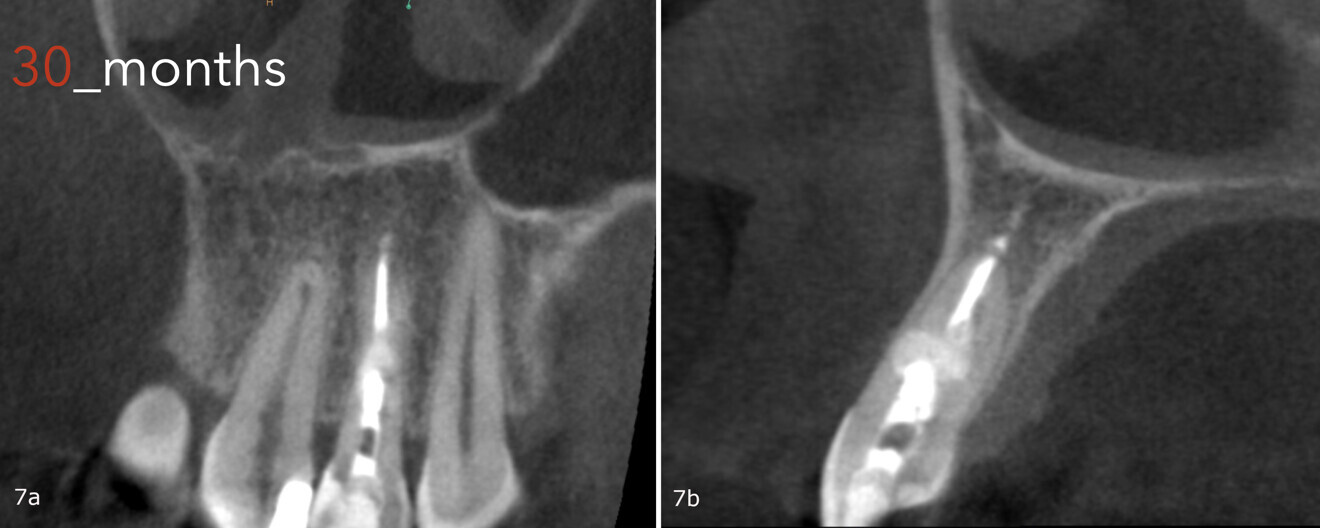

Recall appointments were performed after five and six months (Fig. 5). The bone healing was complete after five months (Figs. 6a-c), and after 30 months, there were no signs of the bone defect, fracture or any other abnormalities (Figs. 7a & b).

Figs. 7a & b: CBCT scan taken 30 months after the treatment, showing the healed lesion.